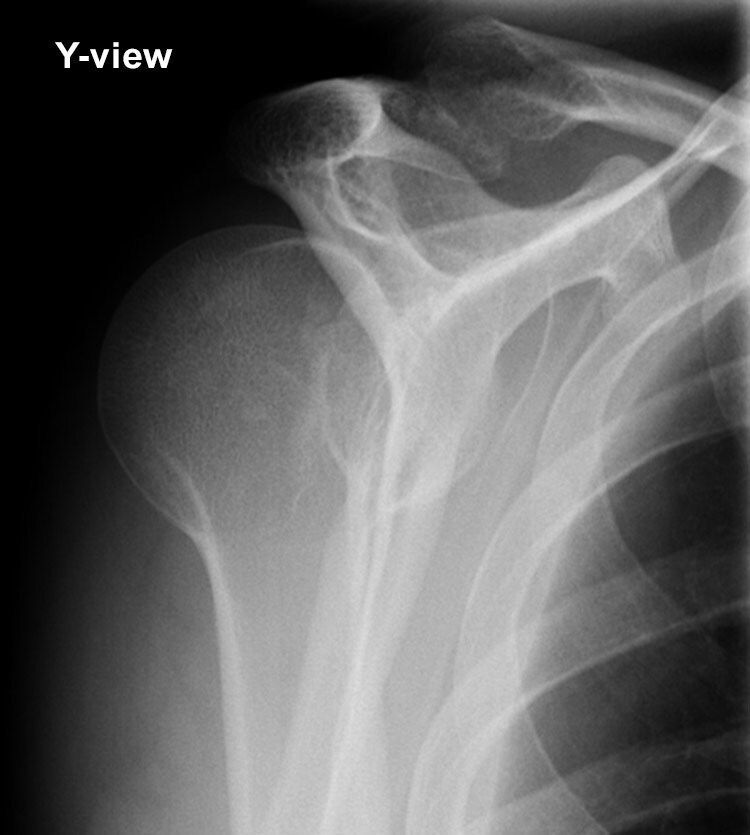

X-RAY QUIZ: Which finding is present on this image?

Start Quiz bit.ly/36i1txn